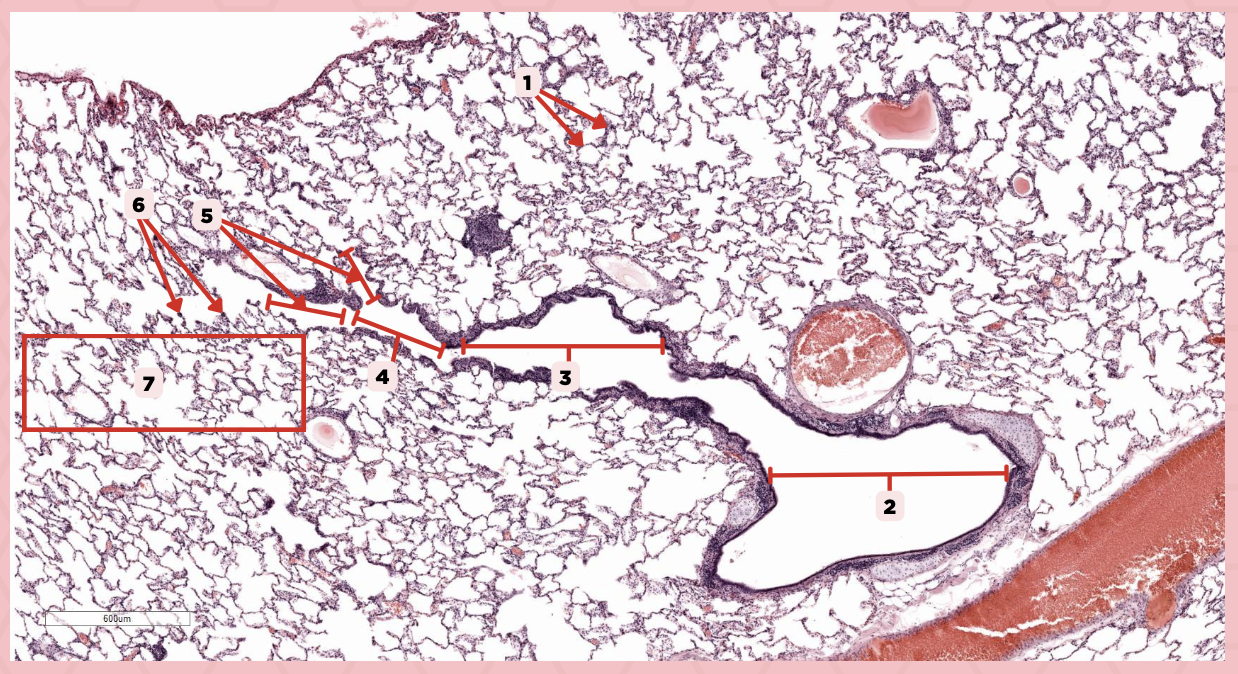

Lumens and Interalveolar septa

Name the irregular spaces and the fine threads of tissue that separate them.

Visceral pleura

Identify the structure labeled as 1.

Alveoli

Identify the structure labeled as 2.

Bigger and smaller intrapulmonary bronchi

What are the two types of intrapulmonary bronchi?

Pseudostratified epithelium (bigger bronchioles), Simple columnar or cuboidal (smaller)

What are the types of epithelium in No. 3?

Interalveolar septa

Identify the structure labeled as 1.

Intrapulmonary bronchi

Identify the structure labeled as 2.

Bronchiole

Identify the structure labeled as 3.

Terminal bronchiole

Identify the structure labeled as 4.

Respiratory bronchiole

Identify the structure labeled as 5.

Alveolar ducts

Identify the structure labeled as 6.

Alveolar sacs

Identify the structure labeled as 7.